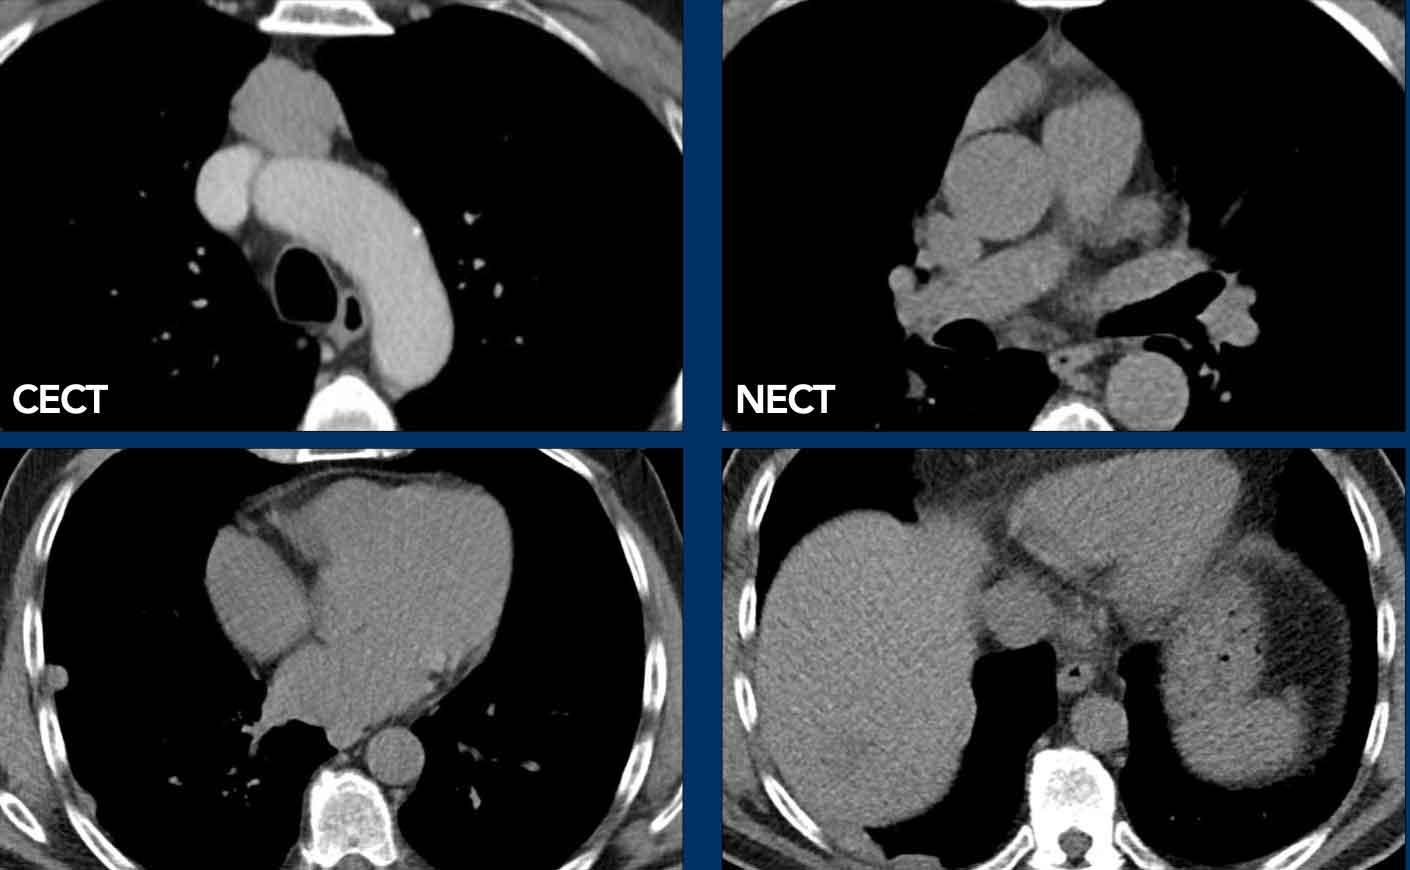

Các hình ảnh này của một phụ nữ 48 tuổi.

Trên MRI toàn thân (TWK-MRI), tình cờ phát hiện một khối ở tuyến ức.

Tiếp tục xem các hình ảnh CT…

Trên CT không tiêm thuốc cản quang (NECT), tổn thương có tỷ trọng mô mềm khoảng 40 HU.

Chẩn đoán có khả năng nhất ban đầu là u tuyến ức (thymoma).

Tổn thương đã được phẫu thuật cắt bỏ và kết quả bất ngờ cho thấy đây là một nang.

Lý giải cho hình ảnh học gây nhầm lẫn này là nang chứa dịch giàu protein, điều này giải thích cho tỷ trọng cao trên NECT.

Hình ảnh trông như ngấm thuốc tương phản trên chuỗi xung T1W có fat saturation có thể là do hiện tượng bão hòa mỡ không đồng nhất.

Tiếp tục xem hình ảnh tiếp theo…

Lưu ý hiện tượng bão hòa mỡ không đồng nhất (mũi tên).

Điều này dẫn đến hiện tượng ngấm thuốc giả (pseudo-enhancement) và chẩn đoán sai.

Chẩn đoán cuối cùng

Nang tuyến ức.